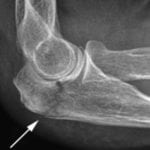

Чаще всего онемение левого предплечья появляется из-за сдавления локтевого нерва в кубитальном канале. Причиной может быть частое монотонное сгибание руки, привычка опираться на локоть, сильный ушиб или травма. Проблема нередко возникает у водителей, которые часто кладут согнутую руку на бортик двери рядом со стеклом.

Для синдрома кубитального канала характерен положительный симптом Тинеля. Он проявляется усилением боли при постукивании пальцем по месту защемления нерва.